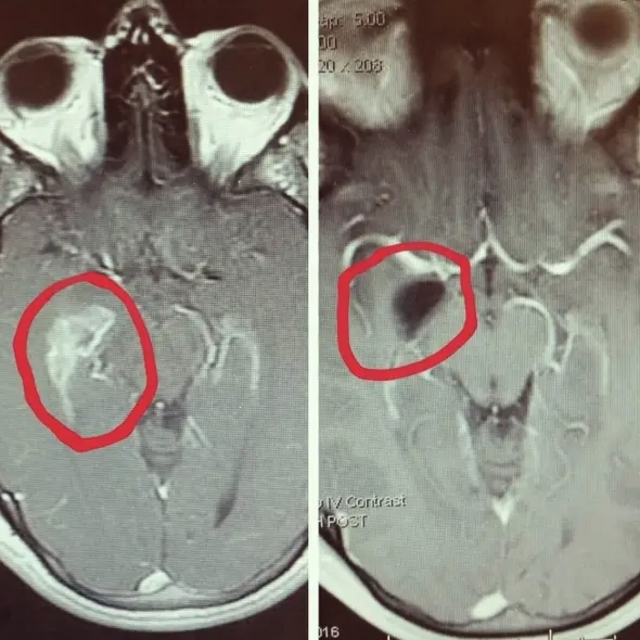

Temporal lobdan bir tümörün alınması için yapılan ameliyattan önce ve sonra çekilen iki beyin MR’ı.